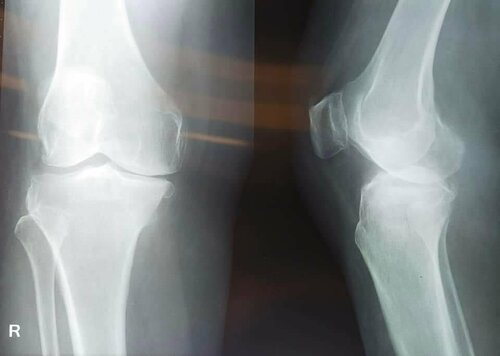

Treatment for Osteoarthritis by Dr. Jagdish Dhake | Knee replacement surgeon Pune

A special case of Knee Replacement is operated by Consultant Orthopedic Surgeon in Pune  Dr. Jagdish Dhake. An osteoarthritis is a common form of...